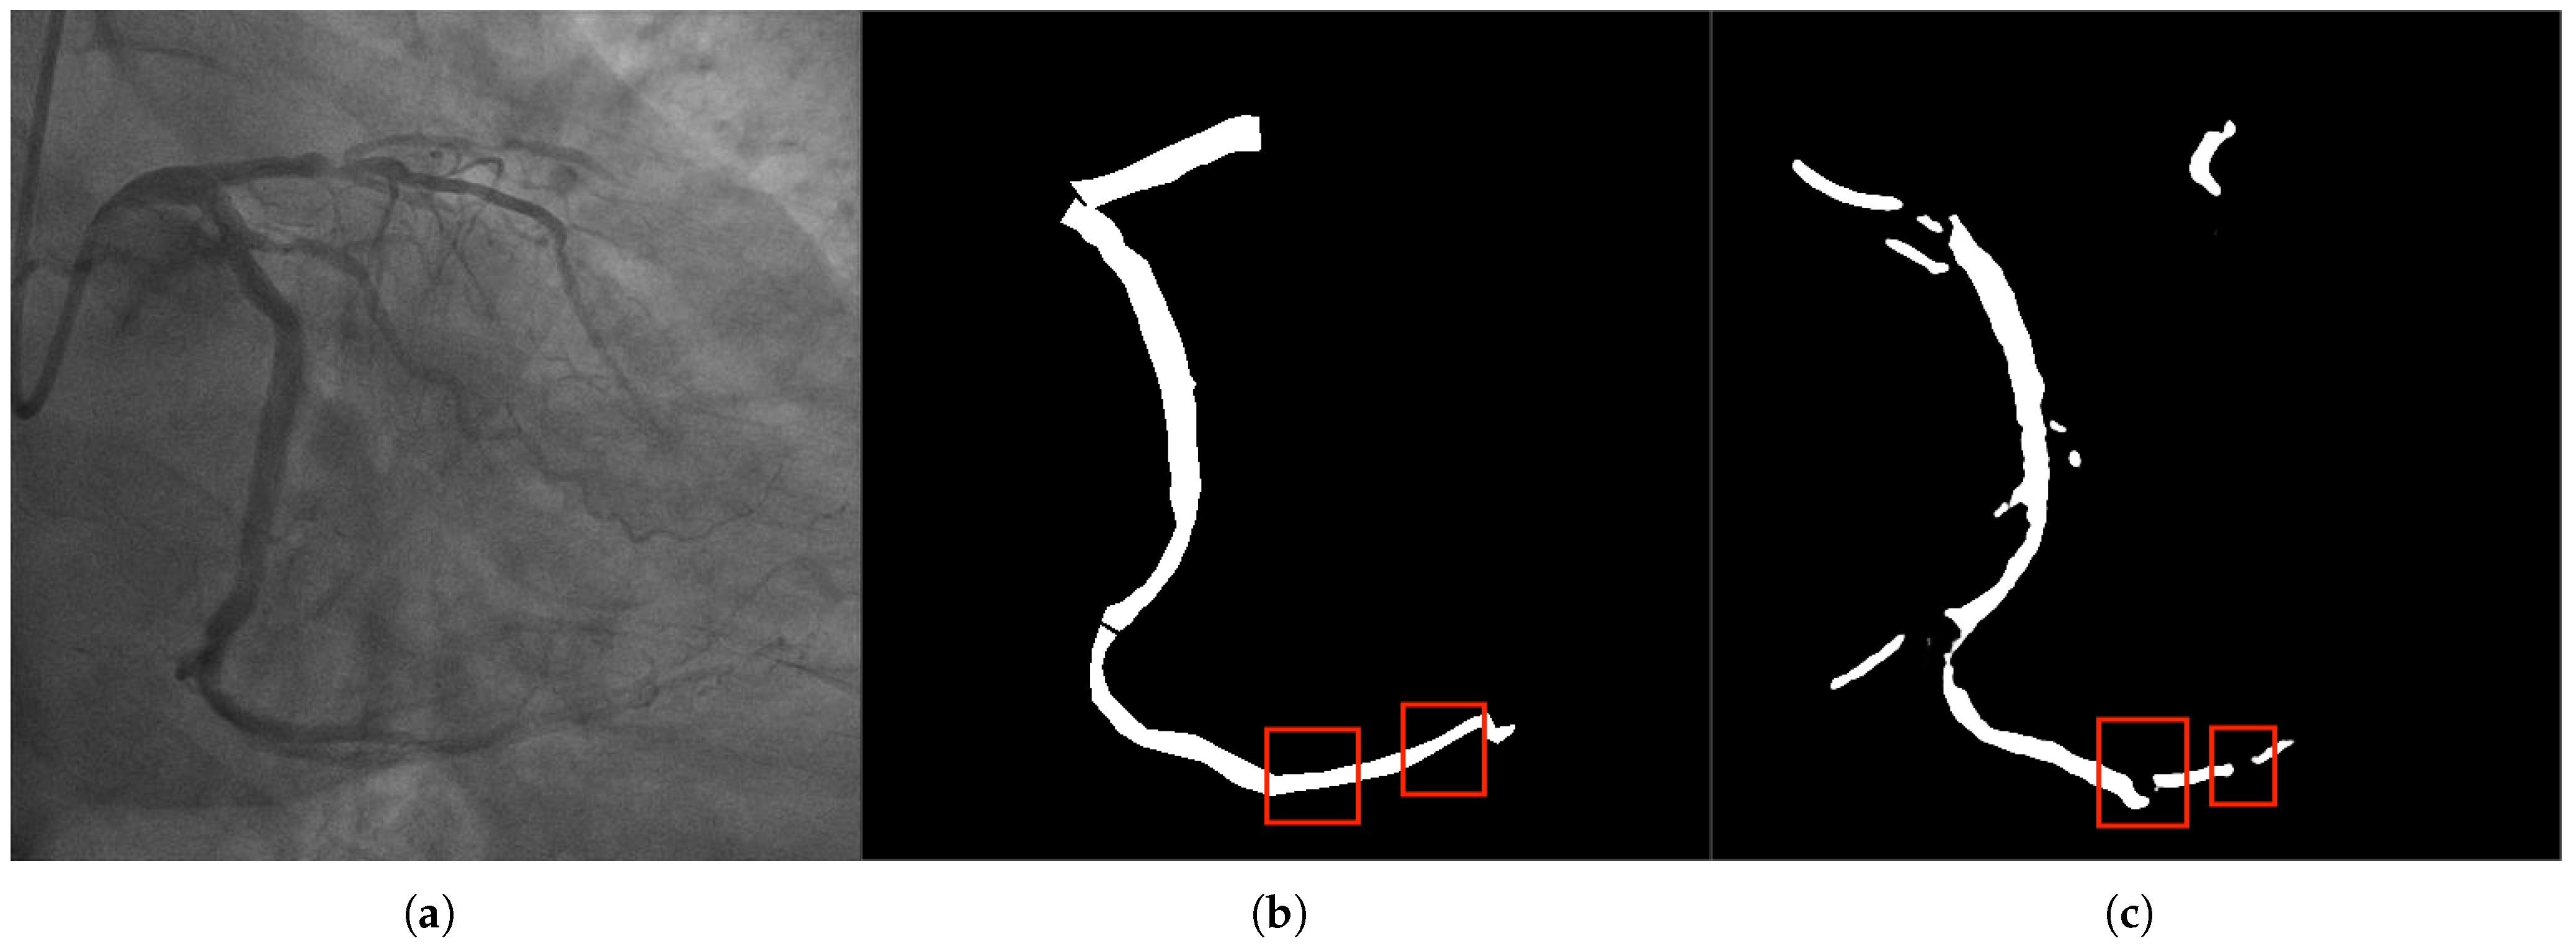

2.2. Key Issues in Coronary Vessel Segmentation

2.2.2. Connectivity Issues